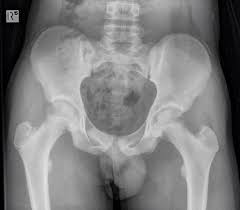

Avulsion Fracture Hip In Teenager / Avulsion Fracture Of The Iliac Crest In A Child / With an avulsion fracture, an injury to the bone occurs near where the bone attaches to a tendon or ligament.

Avulsion Fracture Hip In Teenager / Avulsion Fracture Of The Iliac Crest In A Child / With an avulsion fracture, an injury to the bone occurs near where the bone attaches to a tendon or ligament.. Related online courses on physioplus. I am 15 and did it to my hip/ upper pelvic bone. Try not to move while you're waiting for the ambulance. When the fracture happens, the tendon or these fractures most often affect bones in the elbow, hip, and ankle. With an avulsion fracture, an injury to the bone occurs near where the bone attaches to a tendon or ligament.

Hip pain in children is always a potentially serious and needs urgent assessment. Call 999 and ask for an ambulance. They are serious injuries that most often occur in people aged 65 and older. I am 15 and did it to my hip/ upper pelvic bone. They usually happen when a bone is moving one way, and a tendon or ligament is suddenly pulled the opposite way.

Apophyseal Avulsion Fracture Ric Size from i1.wp.com They are serious injuries that most often occur in people aged 65 and older. People who fracture their hip sometimes need surgery to fix the fracture or replace the hip. These injuries can be extremely painful, and may take months to heal. An avulsion fracture is a fracture in which part of the bone breaks off from the rest of the bone. Sometimes you can get an avulsion fracture in other bones, such as the hand. They are more common in children avulsion fractures are caused by trauma. What causes a hip fracture? Ebraheim's educational animated video describes the condition of avulsion fractures around the hip in adolescence.

Timely, accurate diagnosis is imperative so proper treatment can be initiated. Ebraheim's educational animated video describes the condition of avulsion fractures around the hip in adolescence. Call 999 and ask for an ambulance. I was doing high jump and twisted my body and in the process my muscle ripped my growth bone off. Hip fractures are classified according to their anatomical location as intracapsular, which involves the femoral head and neck, and extracapsular, which includes intertrochanteric, trochanteric, an. With an avulsion fracture, an injury to the bone occurs near where the bone attaches to a tendon or ligament. Symptoms of ankle avulsion fracture are similar to ankle sprain. Call your health care provider if your pain doesn't go away, or if you notice swelling. Preparing for an avulsion fracture in the ankle? Avulsion fractures of the hip and. Avulsion fracture of the iliac crest is an uncommon pathology. This happens when a muscle or tendon connected to the hip bone suddenly tightens so hard that it pulls off part of the bone. I am 15 and did it to my hip/ upper pelvic bone.

With an avulsion fracture, an injury to the bone occurs near where the bone attaches to a tendon or ligament. Anyone can suffer an avulsion fracture of the ankle, but athletes and children are more prone to them than the rest of us. This happens when a muscle or tendon connected to the hip bone suddenly tightens so hard that it pulls off part of the bone. Ebraheim's educational animated video describes the condition of avulsion fractures around the hip in adolescence. An avulsion fracture occurs when a small chunk of bone attached to a tendon or the hip, elbow and ankle are the most common locations for avulsion fractures in the young athlete. If you think you've fractured your hip, you'll need to go to hospital as soon as possible. In acute avulsion fractures, there is usually a clear preceding traumatic incident. When to seek medical help. The causes of hip fracture are very different in young and elderly patients. With age, the bones can become weak and brittle. Other causes include cancer and injury. They usually happen when a bone is moving one way, and a tendon or ligament is suddenly pulled the opposite way. Hip apophyseal injuries in young athletes are a fairly rare problem, and often go unrecognized by health professionals.

Acute Avulsion Of The Iliac Crest Apophysis In An Adolescent Indoor Soccer from www.jbsr.be I am 15 and did it to my hip/ upper pelvic bone. An avulsion fracture is a fracture in which part of the bone breaks off from the rest of the bone. When the fracture happens, the tendon or these fractures most often affect bones in the elbow, hip, and ankle. What causes a hip fracture? There are numerous sites at which these occur. Hip pain in children is always a potentially serious and needs urgent assessment. Teenagers are more likely to have this injury than younger children. Hip fractures can limit mobility and independence.

Pain in the hip area may be referred from the knee joint or from structures in the inguinal canal, testis (including torsion) and lower abdomen, or from the lower back. Teenagers are more likely to have this injury than younger children. The causes of hip fracture are very different in young and elderly patients. Other causes include cancer and injury. Hip fracture occurs in approximately 341,000 persons in the united states each year. Read about causes, treatment options, available mobility devices, tips for recovery, and more. This happens when a muscle or tendon connected to the hip bone suddenly tightens so hard that it pulls off part of the bone. In acute avulsion fractures, there is usually a clear preceding traumatic incident. A hip fracture is a break in the bones of your hip. A hip fracture is a common injury, especially in people with osteoporosis. I was doing high jump and twisted my body and in the process my muscle ripped my growth bone off. A broken hip in older people is often partly the result of weakening bones from osteoporosis. This most commonly occurs at the ischial tuberosity where the hamstrings attach, or the iliac pain at the bony part on the front of the hip may be an anterior superior iliac spine avulsion fracture.